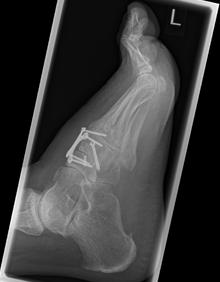

2.-Postoperatives Bild Februar 2017

Die indizierte Operation wurde im Februar 2017 durchgeführt. Die Stabilisierung der Arthrodese erfolgte mit insgesamt 3 Schrauben und Anlagerung vom Knochenersatzmaterial.